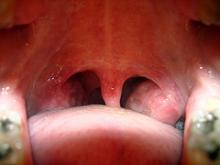

The proposed mechanism of benefit from the surgery is that it removes an important source of circulating pathogenic T-cells generated in the palatine tonsils. The T-cells respond to antigenic short peptides common to streptococcal M-protein and skin keratins, Dr. Ragna Hlin Thorleifsdottir explained at the annual congress of the European Academy of Dermatology and Venereology.

The link between psoriasis and strep throat may be pathogenic T-cells generated in palatine tonsils.